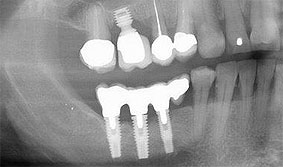

Implantate werden zum Ersatz verloren gegangener Zähne gesetzt.

Sie ermöglichen so das Wiederherstellen der Kaufunktion ohne Nachbarzähne zu beschleifen, einen herausnehmbaren Zahnersatz zu vermeiden oder einer Prothese zu einem festeren Halt zu verhelfen.

Voraussetzung ist ein vollständig eingeheiltes, freigelegtes Implantat, das mit einer Suprakonstruktion in Form von Kronen, Brücken oder Prothesen versorgt wird. Zahnlücken können so geschlossen werden und ein Wiederherstellen der Kaufunktion wird ermöglicht.

Auch hier unterscheidet man, wie beim zahnbefestigten Zahnersatz festsitzenden und kombiniert festsitzenden- herausnehmbaren Zahnersatz.

Ganz besonders Totalprothesenträgern kann auf diese Weise zu besserem Halt verholfen werden und die zum Teil unangenehme Gaumenabdeckung kann oftmals vermieden werden.